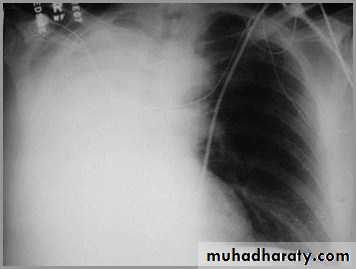

Differentiating the Causes of an Opacified Hemithorax

Atelectasis of an entire lungA large pleural effusion

Atelectasis of the Lung

There is a shift of heart and hemidiaphragm toward side of opacification (toward side of volume loss)Pleural Effusion